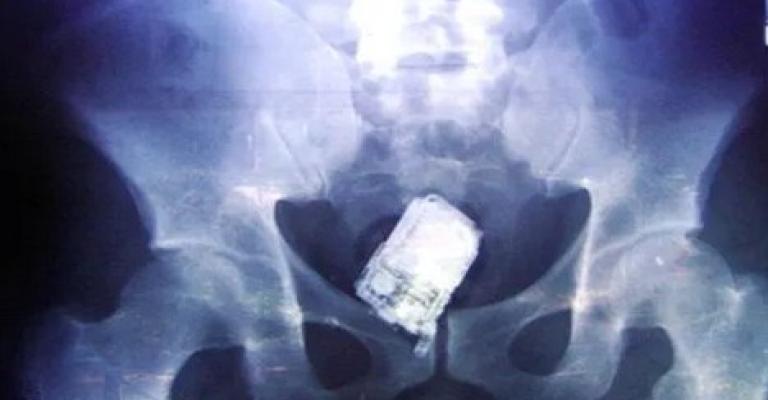

نفى وزير الصحة الدكتور سعد جابر صحة فيديو وخبر مفبرك يشير الى نسيان احد الاطباء هاتفه في بطن مريضة . وقال جابر ان الفيديو تم تداوله عام 2015 وتم نفيه أنذاك لعدم صحته. وقال: ان وزارة الصحة نفت الحادثة